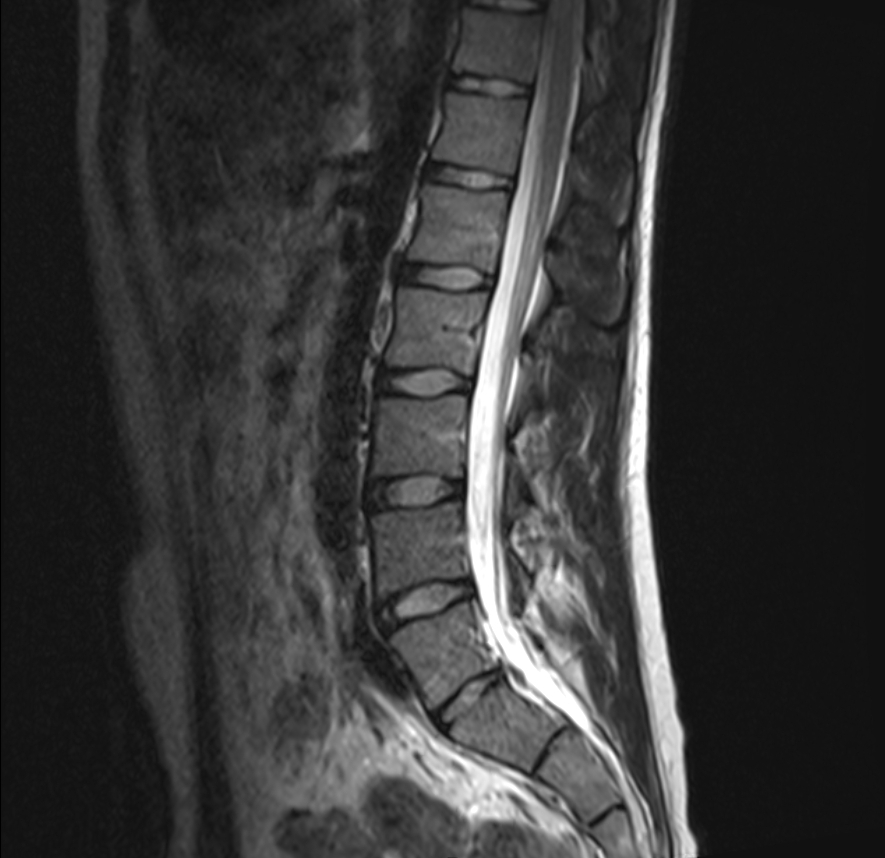

In der modernen Radiologie spielt die Zweitbefundung eine entscheidende Rolle,

um die bestmögliche Diagnosesicherheit zu gewährleisten. Sie bietet Patienten

und Ärzten eine zusätzliche Ebene der Absicherung, indem sie eine unabhängige

Überprüfung der bereits gestellten Diagnose durch einen zweiten Radiologen

ermöglicht. Diese Praxis kann besonders wertvoll sein, wenn es um komplexe

oder seltene Krankheitsbilder geht, bei denen eine präzise und genaue Diagnose

unerlässlich ist.